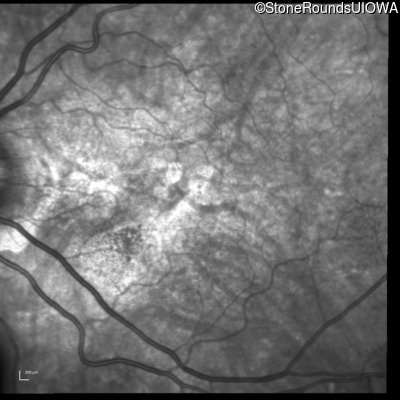

Fluorescein Angiography - Right - 20/20 -3 sc

Exemplar